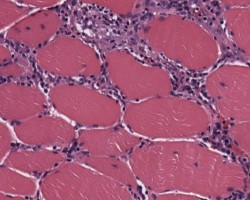

- Muscle biopsy shows endomysial and perivascular monocytic inflammation and necrosis with regeneration.